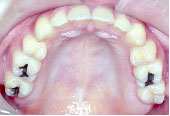

After

術前矯正がうまくいったので術後矯正は微調整で済みました。

骨が固まり安定するまで待って装置をはずします。

あごのずれもなくなり、バランスのとれた美しい口元になりました。咬み合わせも非常に良くなってご本人は大変満足されています。

治療期間は3年7か月です。